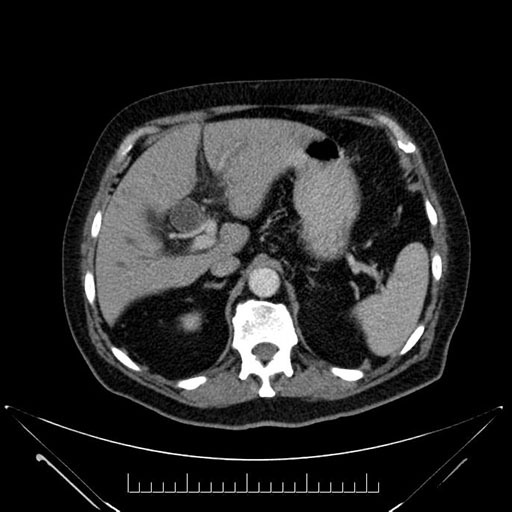

Imaging Analysis

Look through the patient's CT scan to identify any areas of concern for the necessary procedure.

Based on your CT findings, which issue(s) would give reason for "planned slowing down moment(s)" in this case?

Considering a standard Whipple procedure, what step(s) of the operation would you do differently in this case?